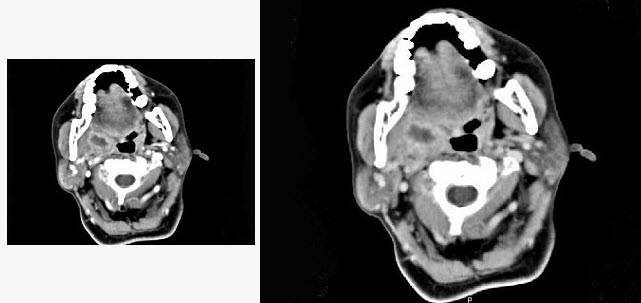

18、单项选择题

女,52岁,咽喉部疼痛半个月,伴低热,CT如图所示,可能诊断为()。

A.咽旁脓肿

B.咽部神经鞘瘤

C.鼻咽血管纤维瘤

D.咽旁淋巴瘤

E.咽旁转移癌